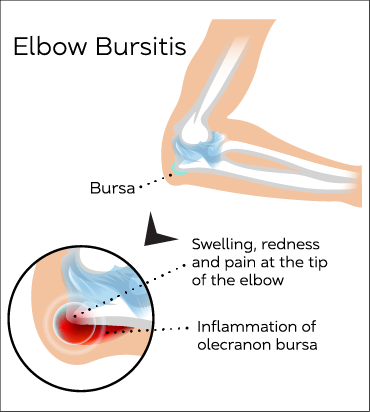

Olecranon Bursitis

Olecranon Bursitis is caused by the inflammation of the fluid sac that is between the olecranon (point of the elbow) and the skin.

Olecranon Bursitis is a common condition.

Common symptoms include localised swelling and tenderness, pain on movement, and redness.

Ultrasound guided aspiration (removal of fluid) followed by injection of local anaesthetic combined with corticosteroid often gives a large amount of symptomatic pain relief.